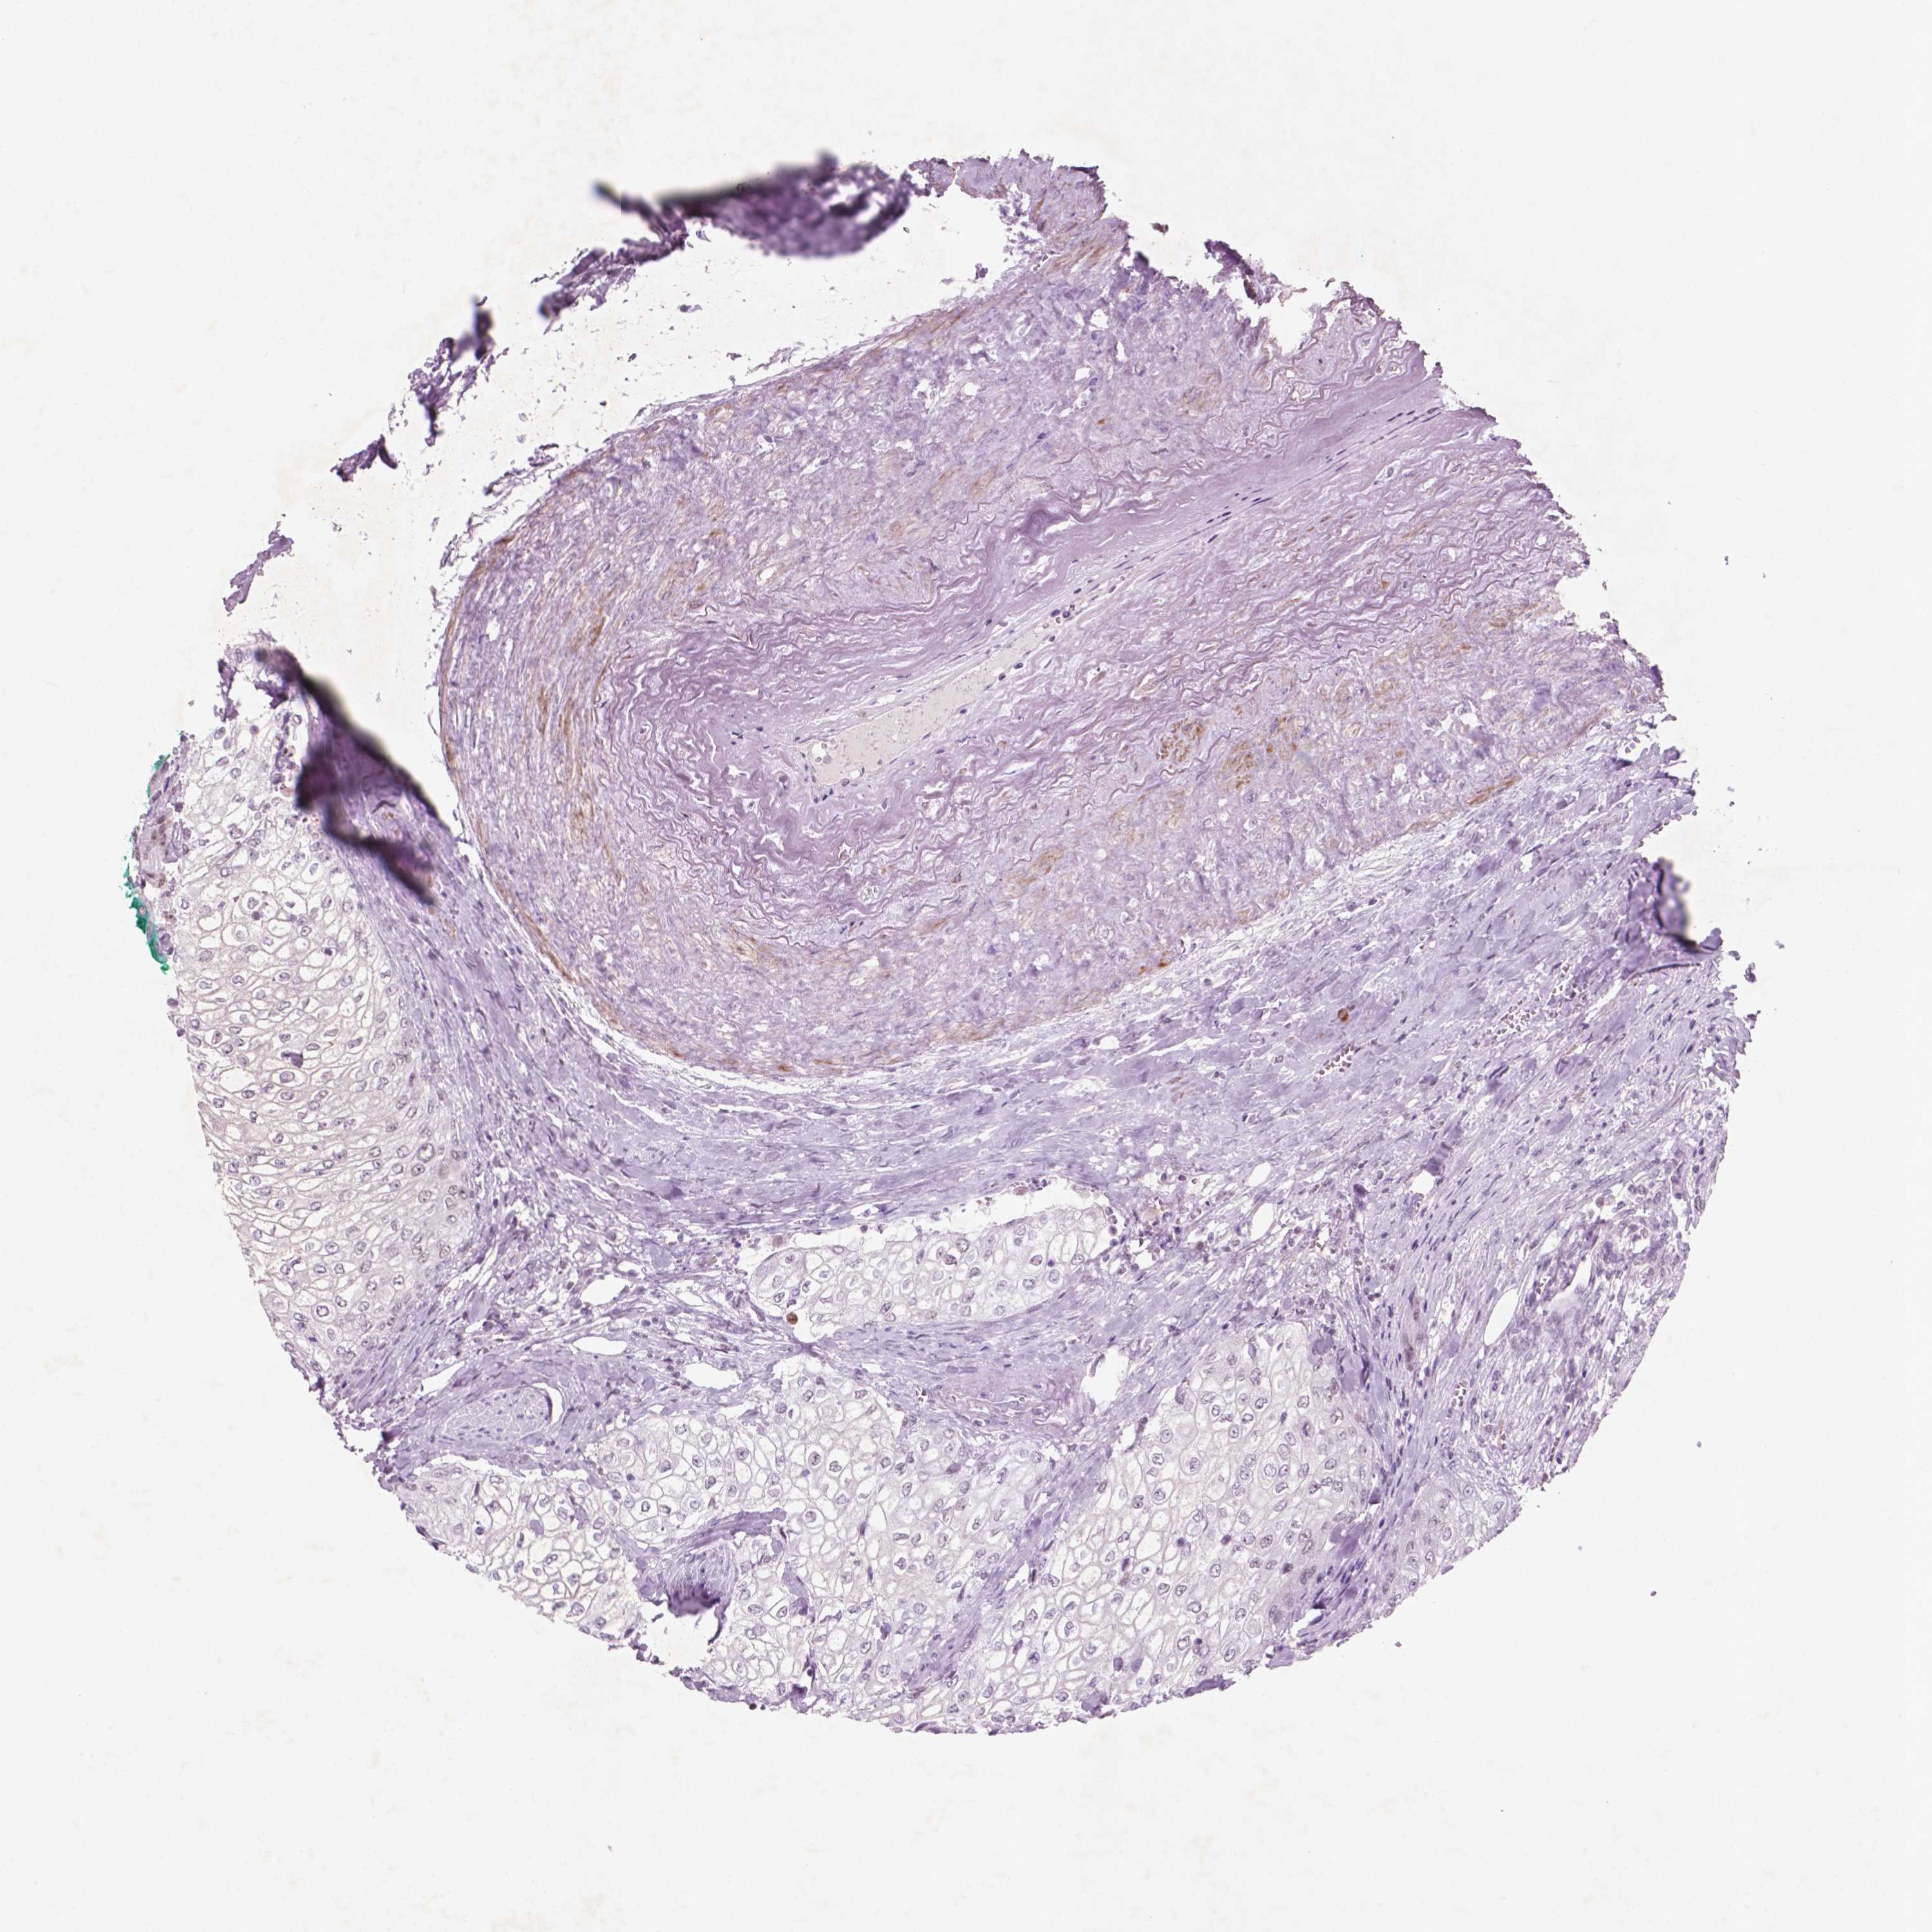

UROTHELIAL CANCER - Protein expressioni

A mouse-over function shows sample information and annotation data. Click on an image to view it in a full screen mode. Samples can be filtered based on level of antibody staining by selecting one or several of the following categories: high, medium, low and not detected. The assay and annotation is described here.

Note that samples used for immunohistochemistry by the Human Protein Atlas do not correspond to samples in the TCGA dataset.

Antibody stainingi

Antibody staining in the annotated cell types in the current human tissue is reported as not detected, low, medium, or high, based on conventional immunohistochemistry profiling in selected tissues. This score is based on the combination of the staining intensity and fraction of stained cells.

Each image is clickable and will lead to virtual microscopy that enables deeper exploration of all samples and also displays staining intensity scores, fraction scores and subcellular localization as well as patient and tissue information for each sample.

Antibody HPA068122

Staining

High

Medium

Low

Not detected

Intensity

Strong

Moderate

Weak

Negative

Quantity

>75%

75%-25%

<25%

None

Location

Nuclear

Cytoplasmic/membranous

Cytoplasmic/membranous,nuclear

Urothelial carcinoma, High grade

Urothelial carcinoma, NOS

Urothelial carcinoma, Low grade